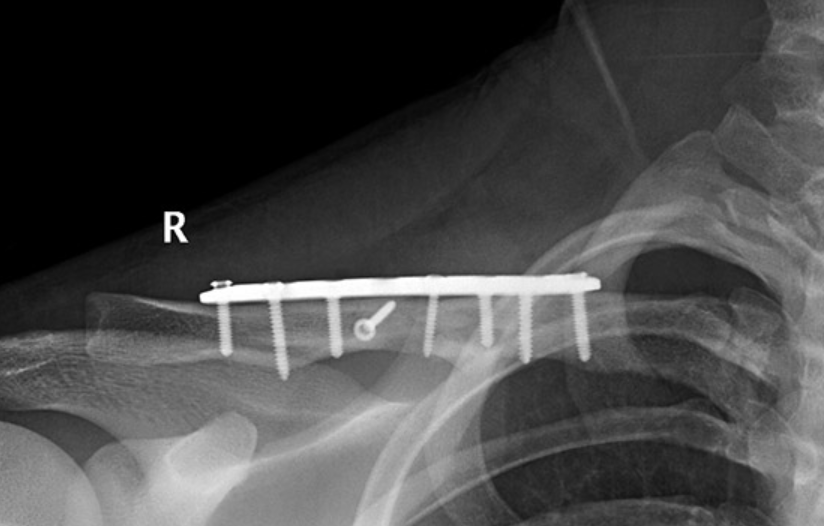

How is Orthopaedic Fracture Fixation Performed?

The broken bone is aligned and fixed with metal implants that hold it until it heals naturally.